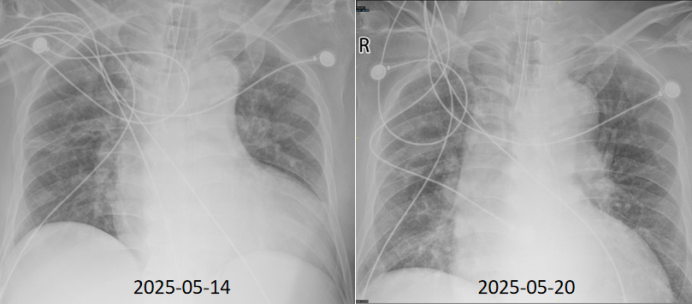

5月14日和5月20日复查胸片(图17)

17  复查胸片

以舒巴坦/度洛巴坦为基础的抗感染方案应用后患者热峰较前下降(图18)

18  患者入院第4周与第3周时相比热峰下降